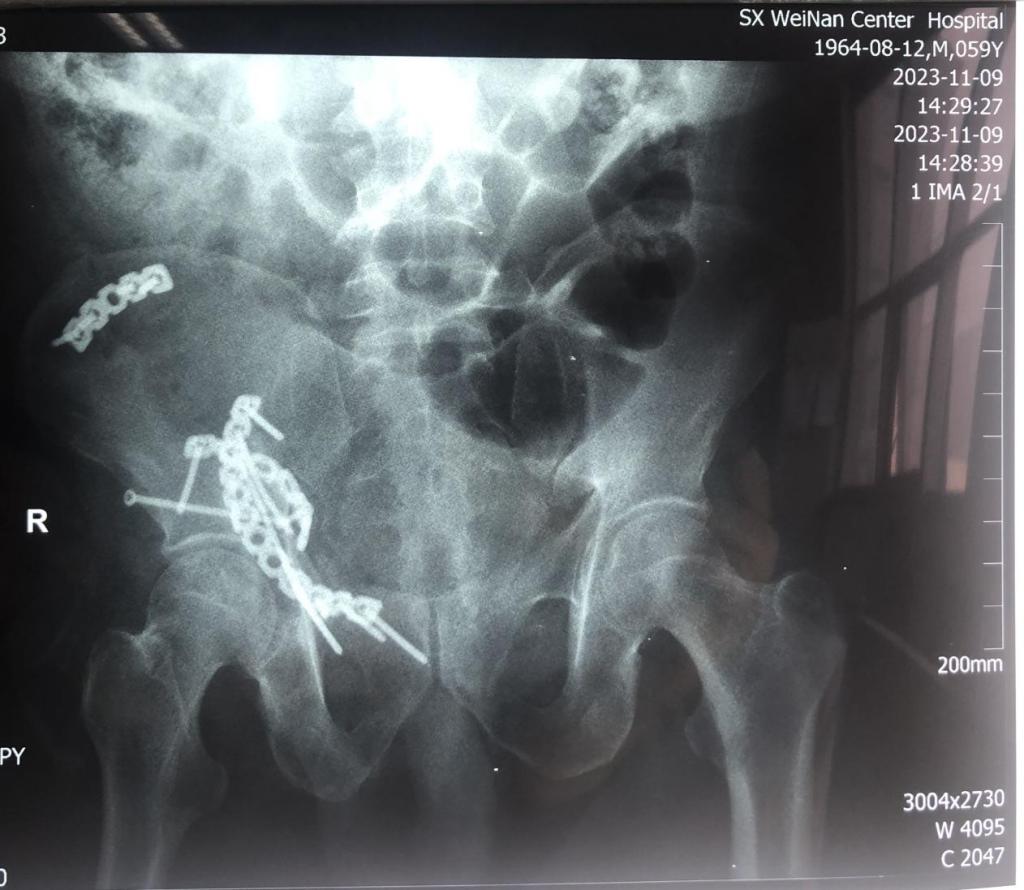

患者车祸致伤入院后,李玉民主任医师组织科内多次讨论认为,该患者为高能量损伤致复杂髋臼骨折,Letournel-Judet分型为高位前柱伴后半横骨折,股骨头中心脱位致臼顶、四方体粉碎性骨折,后柱横断向后方移位,前柱高位骨折伴旋转移位,头臼不匹配,臼内台阶明显,髋关节失去正常形态,失去明显的解剖标志,严重功能受限。须尽早积极手术治疗,否则后期出现畸形愈合关节功能丧失,股骨头坏死,致残率增高失去劳动能力。

经严谨的术前规划及方案设计,117号由郭宏军主任医师医疗组给予单一前方经腹直肌旁入路手术内固定。术后患者右髋关节功能恢复良好,自行翻身,半靠体位均不受限。

该患者伤后三周手术,骨折端已明显骨痂包绕,显露不易,术后给予高位前柱截骨使得髋臼骨折易于解剖复位固定,恢复了髋臼关节面光滑连续完整,头臼匹配良好,预防了股骨头后期坏死,使患者能够早期功能锻炼,最大程度减少了致残率,早日恢复劳动力。